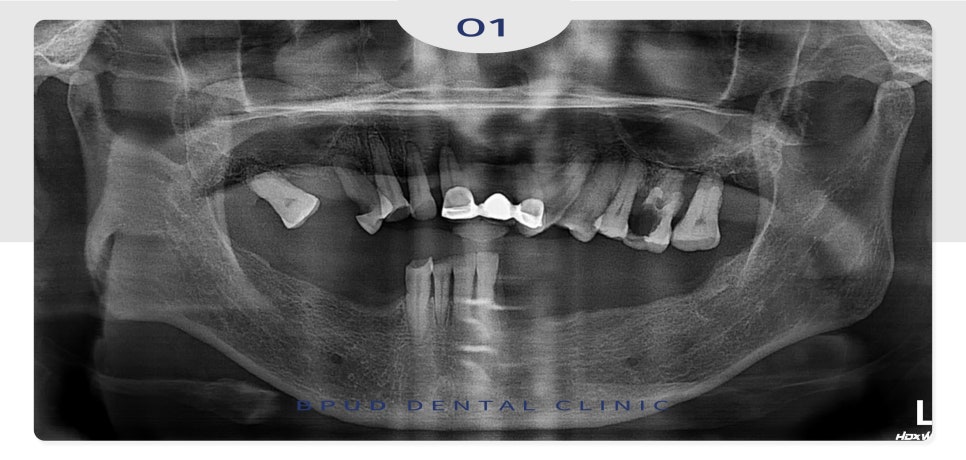

환자분께서 처음 내원해 주셨을 때,

구강 내 전반적으로 상실된 부위와

심하게 충치가 진행된 부위를 발치하고

전체적으로 임플란트 식립을 진행하였는데요.